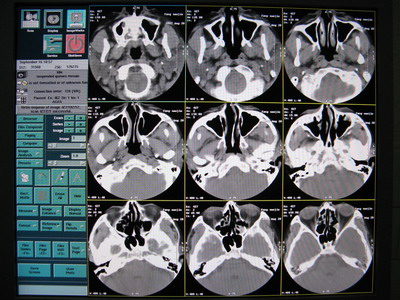

CT掃描圖像出現偽影,偽影圖像如下:

出現的頻率很高,且無規律,查看Error log,無報錯。